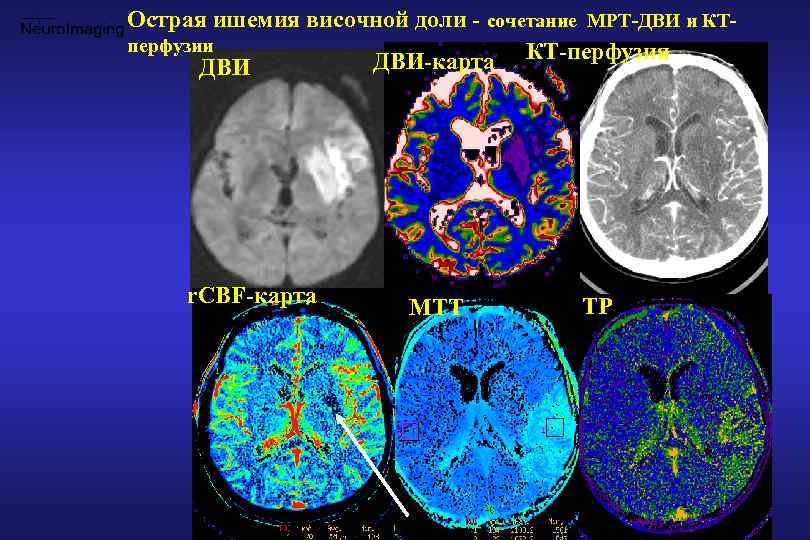

Хроническая ишемия головного мозга и лейкоареоз: симптомы и лечение